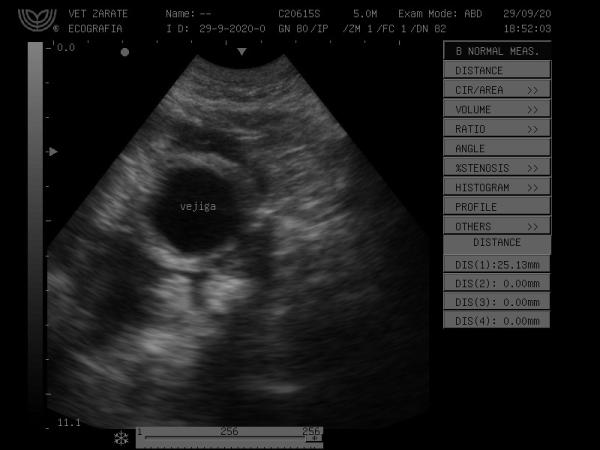

A MI PERRO SE ENCUENTRA CON UN PROBLEMA HEPATICO LO TIENE INFLAMADO Y PARTE LE ENCONTRARON UNA MASA ADERIDA QUE EN MAS O MENOS LE VAN A VOLVER A SACAR UNA NUEVA ECOGRAFIA, ACTUALMENTE SE ENCUENTRA CON TRATAMIENTO DE SILIMARINA DE 300GR X CADA 12 HORAS Y URSOVET 5ML X CADA 12 HORAS, ADICIONALMENTE ME RESENTARON VET LIFE HEPATICO COMO DIETA, A ESO JUSTAMENTE QUIERO SABER SI YO PUEDO HACERLE SU DIETA, ESPERO ME PUEDAN AYUDAR